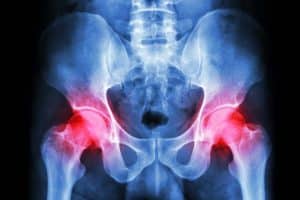

The pelvis is a crucial part of your body, housing organs like the bladder, uterus (in individuals assigned female at birth), and rectum. Optimal pelvic health is essential for various bodily functions, including urination, bowel movements, sexual activity, and overall stability.